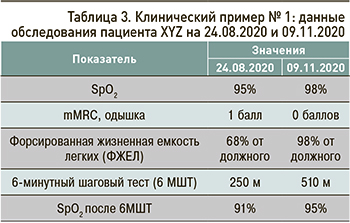

Данные обследования пациента XYZ, проведенного 24.08.2020 и 09.11.2020, отражены в таблице 3.